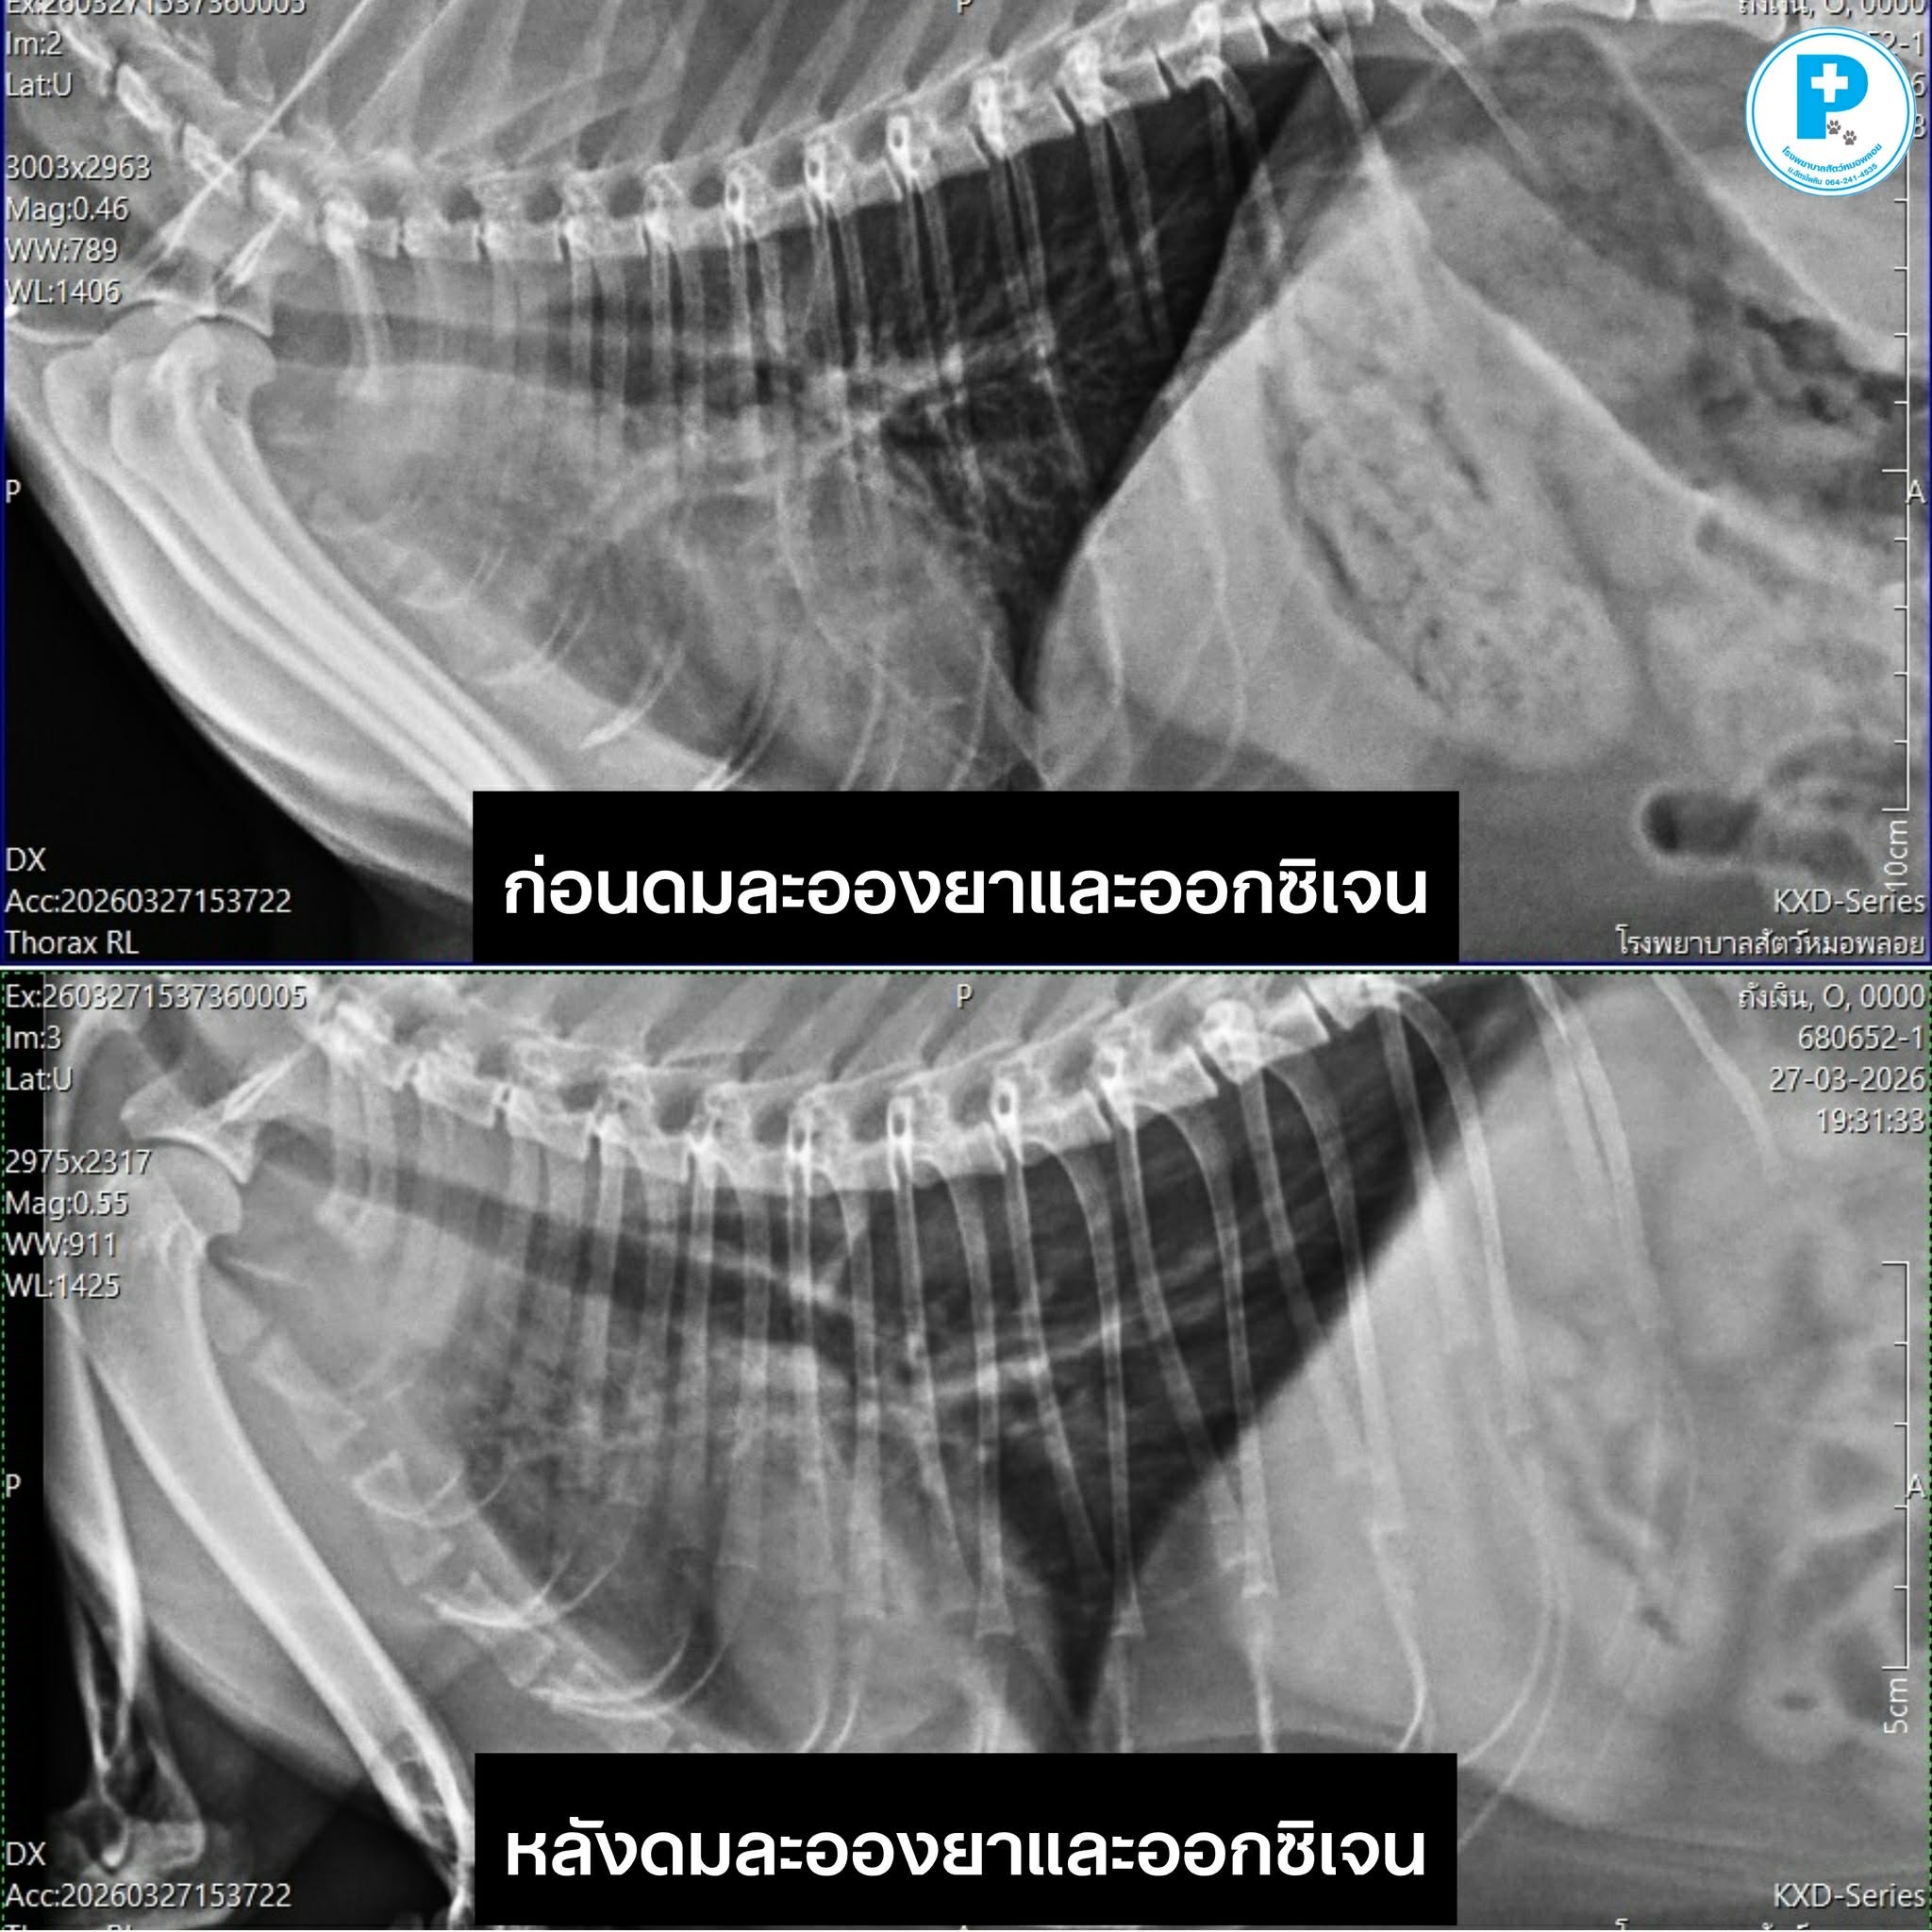

1. X-ray (การวินิจฉัย): เพื่อดูโครงสร้างภายในปอดและหัวใจ อย่างในเคสนี้ภาพรังสีเผยให้เห็นภาวะ Lung Atelectasia (ปอดแฟบ) ซึ่งในน้องถังเงินมักมีสาเหตุโน้มนำมาจาก Asthma (หอบหืด) ทำให้เกิดเมือกอุดตันในหลอดลมจนลมเข้าสู่ปอดบางส่วนไม่ได้

2. Oxygen Therapy (การประคับประคอง): สำคัญมากในแทบทุกเคส เพราะการให้ออกซิเจนและการพ่นยาช่วยลดความเหนื่อยล้าของร่างกาย ทำให้น้องหายใจได้สบายขึ้นอย่างเห็นได้ชัด (สังเกตจากภาพเปรียบเทียบ Before & After ที่น้องดูผ่อนคลายลงหลังได้รับออกซิเจนและพ่นละอองยาครับ)